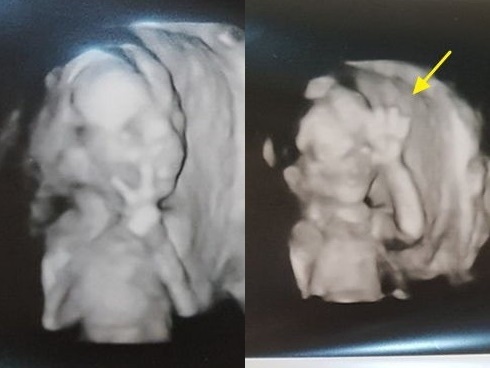

- Tuần thứ 30 - 32: Vào giai đoạn này, bằng phương pháp siêu âm bác sĩ sẽ phát hiện ra những bất thường ở động mạch, tim, não của thai nhi. Ngoài ra dây rốn, vị trí nhau thai và tình trạng nước ối cũng được kiểm tra.